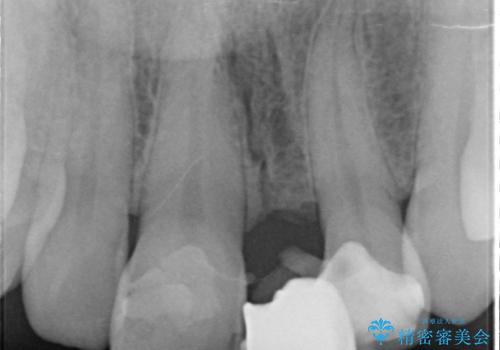

- 前歯の歯並びや色が気になるといらっしゃった方の症例です。

前歯4本をオールセラミッククラウンで補綴することで、歯の並びや色の改善を行いました。